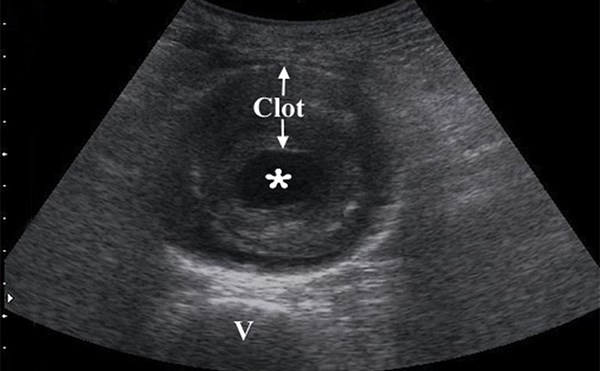

Renal